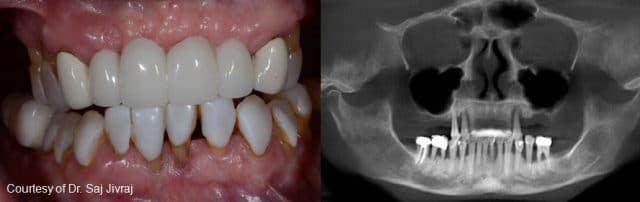

The All-on-4® treatment concept is a cost-efficient, graftless solution that provides patients with a fixed full-arch prosthesis on the day of surgery.

- Full-arch rehabilitation with only four implants

- Two straight anterior implants and two implants tilted up to 45º in the posterior

- Immediate Function (fixed provisional bridge)